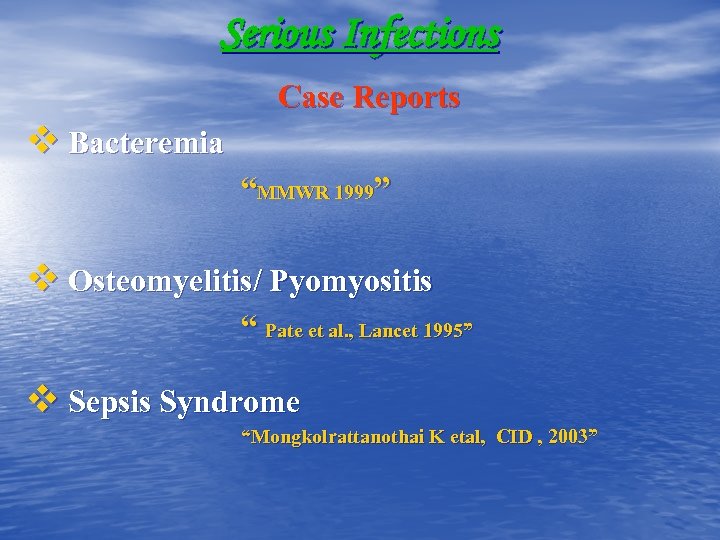

Serious Infections Case Reports v Bacteremia “MMWR 1999” v Osteomyelitis/ Pyomyositis “ Pate et al. , Lancet 1995” v Sepsis Syndrome “Mongkolrattanothai K etal, CID , 2003”

Serious Infections Case Reports v Bacteremia “MMWR 1999” v Osteomyelitis/ Pyomyositis “ Pate et al. , Lancet 1995” v Sepsis Syndrome “Mongkolrattanothai K etal, CID , 2003”